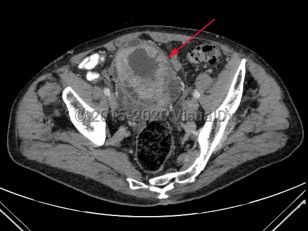

Bladder cancer

Patients with bladder cancer typically present with painless gross or microscopic hematuria, although dysuria, frequency, and urgency may be the presenting symptoms. Diagnosis may be delayed due to the similarity of these symptoms to benign conditions such as urinary tract infections, nephrolithiasis, cystitis, or prostatitis. Urothelial cancer may mimic bladder cancer. In patients younger than 50 years, asymptomatic microscopic hematuria is rarely associated with bladder cancer.